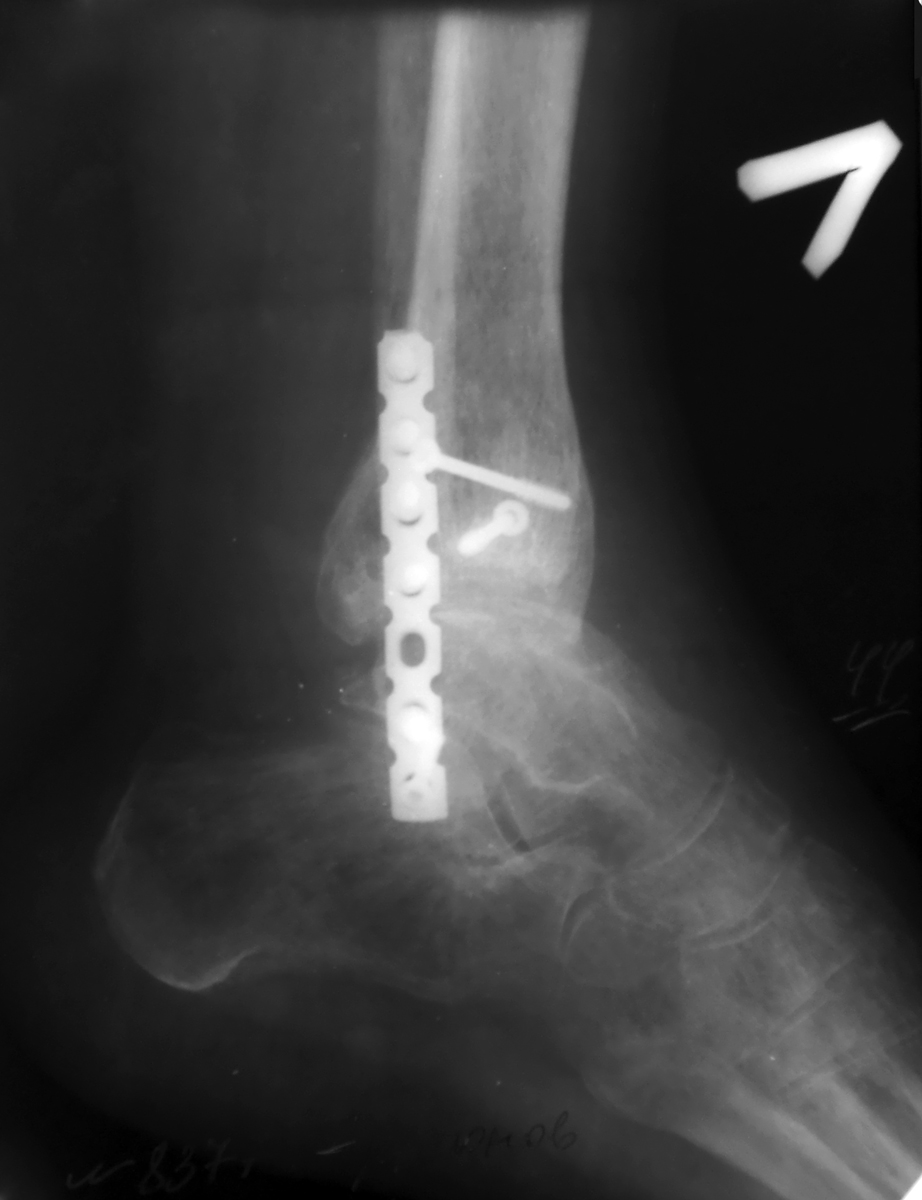

В приложении рентгенограмма первичная. После чего стала ясна сомнительность перелома пилона))) Перелом лодыжек с импрессией суставной поверхности большеберцовой кости в области внутренней лодыжки. На выполненном вчера КТ голеностопного сустава: в просвете сустава определяется клиновидной формы фрагмент костной плотности размером до 13,5х3,5 мм, находящийся в задне-латеральных отделах сустава.

Боковая проекция. Боковой проекции первичных рентгенограмм нет, утеряны больным.